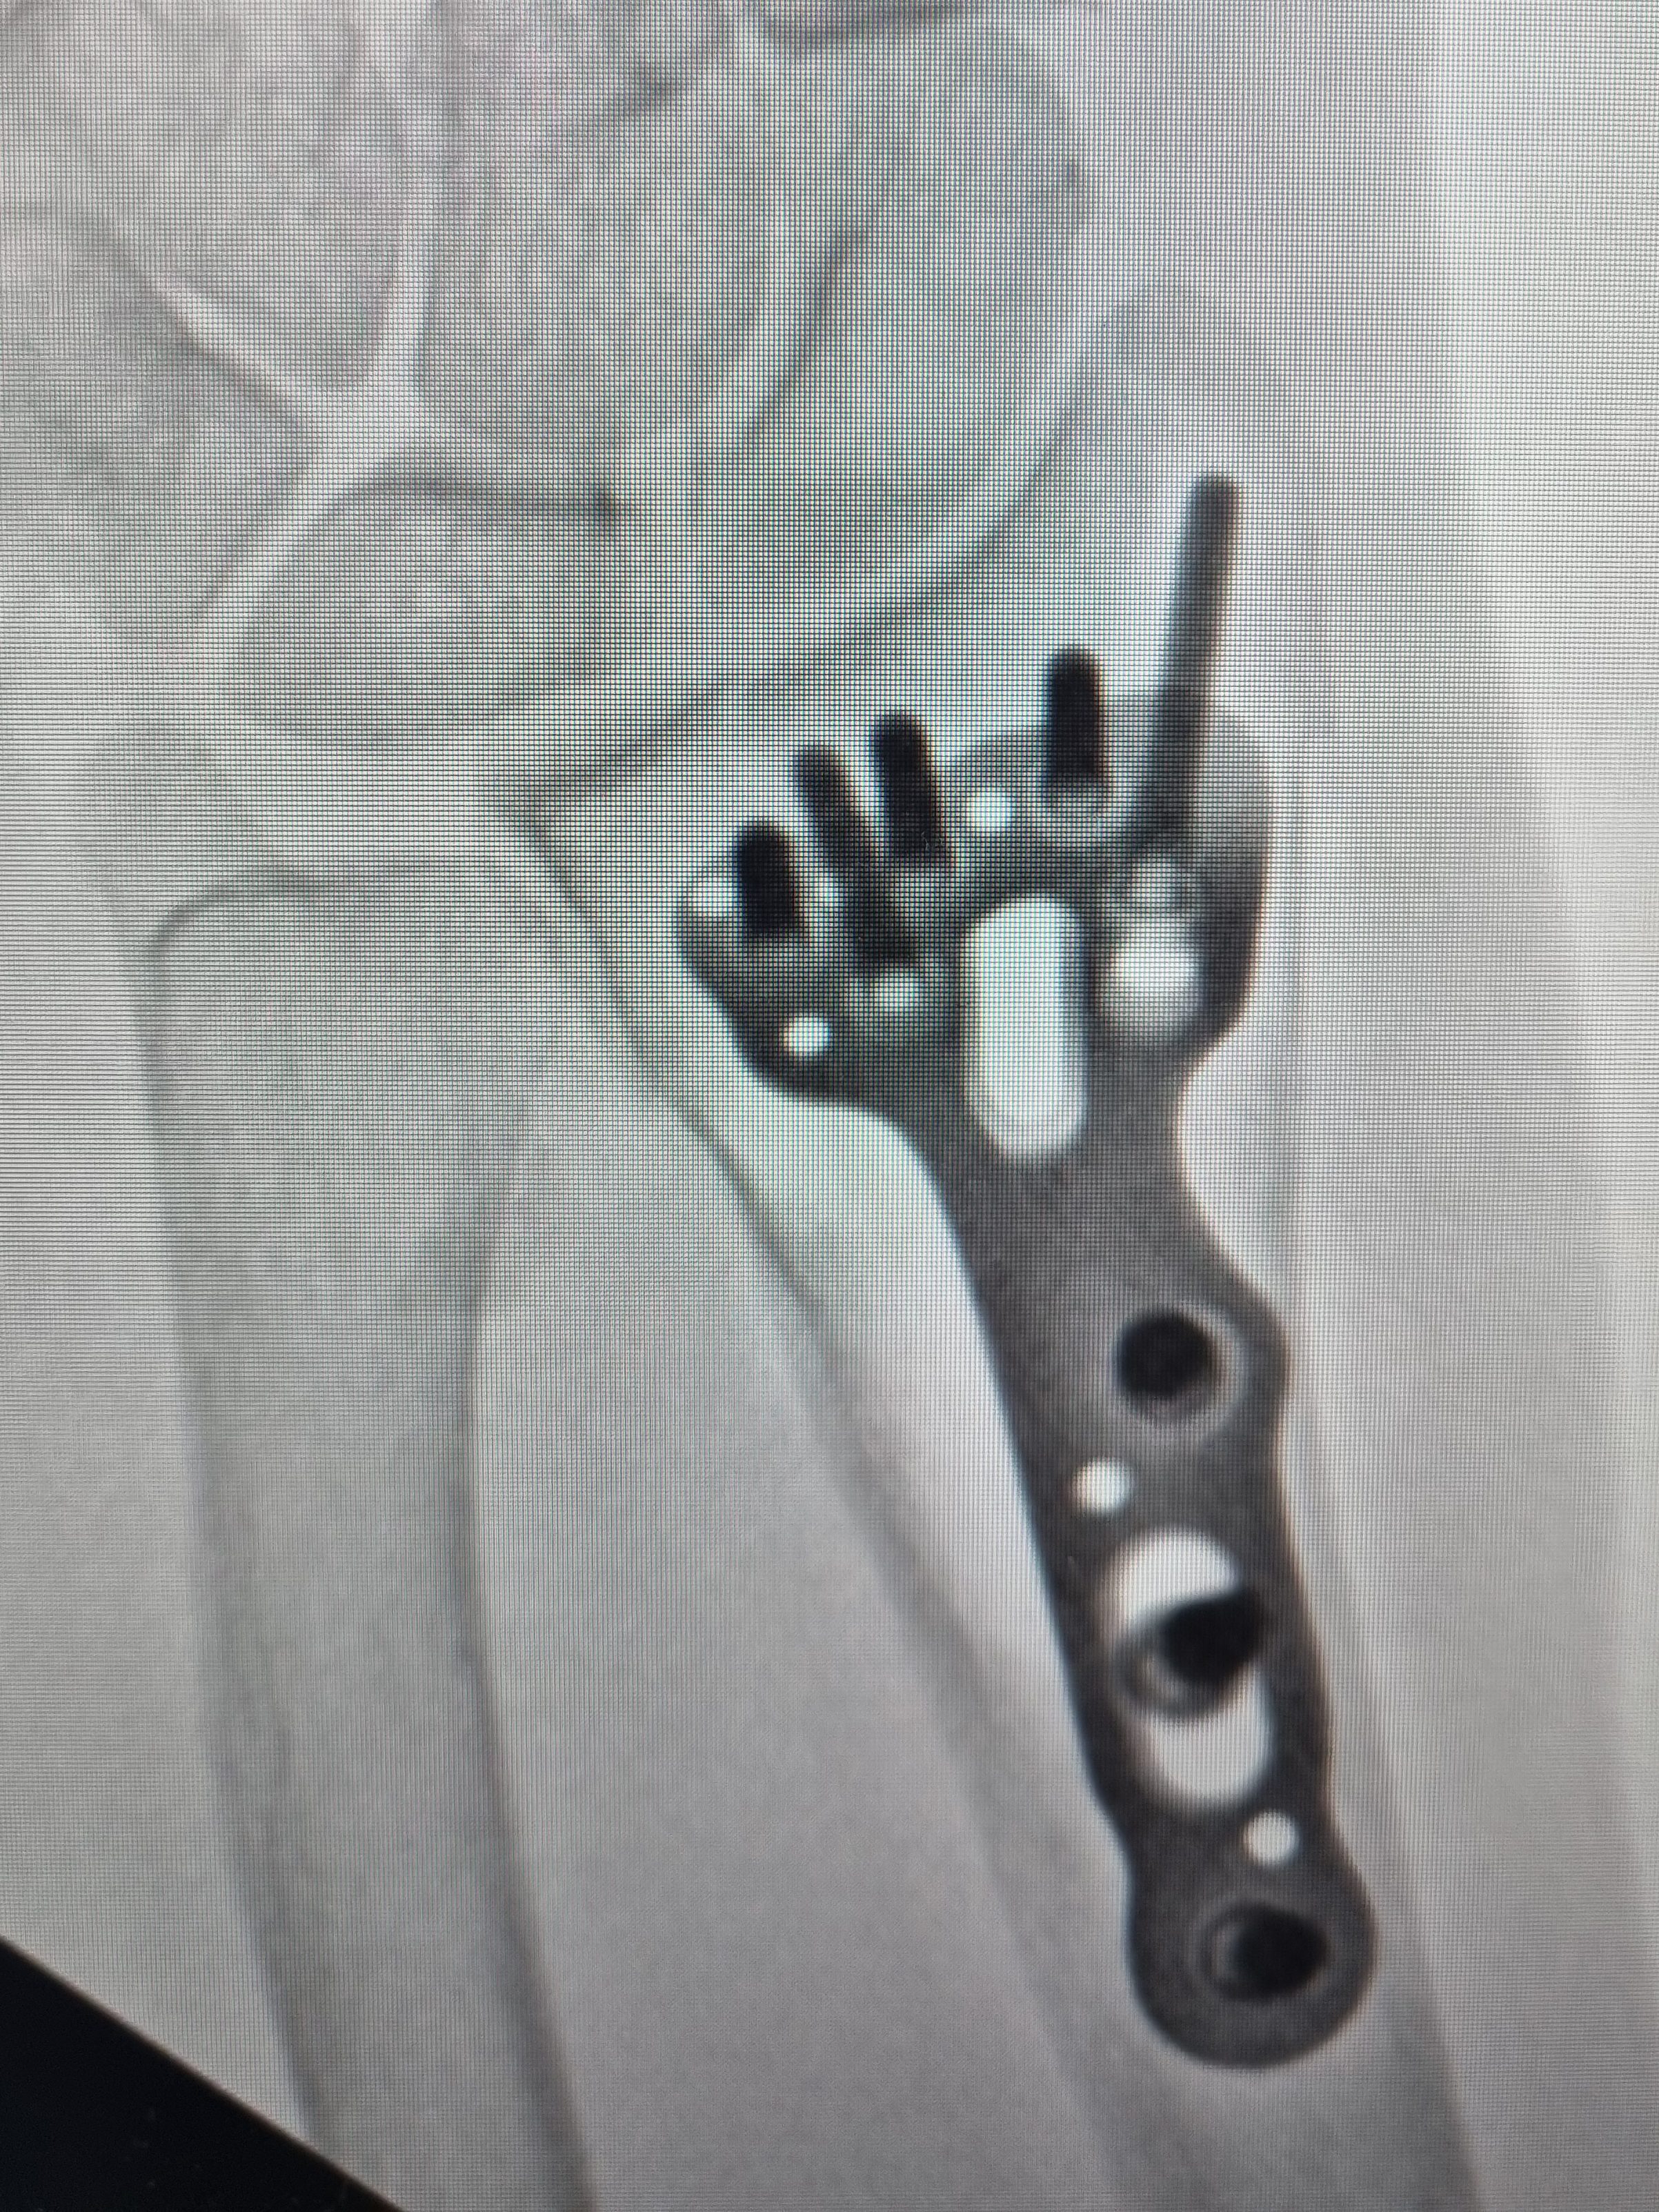

No caso de fraturas instáveis, ou com alta probabilidade de instabilidade, deve-se optar pelo tratamento cirúrgico, a fim de aumentar as chance de consolidação do osso em uma posição mais próxima do ideal possível. Para esse fim, utiliza-se materiais de síntese, as famosas placas e parafusos.

Exemplo de fratura da extremidade distal do rádio tratado com placa e parafusos